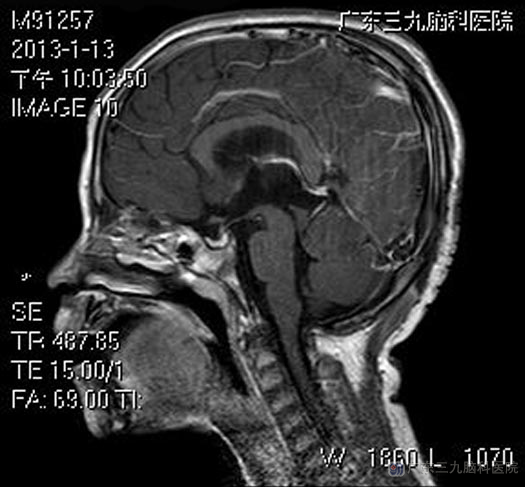

综合神经外科 鲁明主任主刀,在全麻下行右侧枕角外引流+右侧枕部经小脑幕入路(Popen入路)松果体区肿瘤切除术,见肿瘤呈红色,血供丰富,边界清楚,予肿瘤整块分离取出。术后小宝未出现手术并发症,头痛症状消失。病理结果为:(松果体区)不成熟型畸胎瘤 I级。

▲术后MR